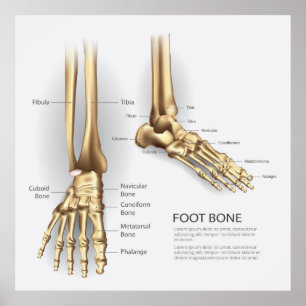

Poster Dessin anatomique des os du pied

Prix32.95 CHF